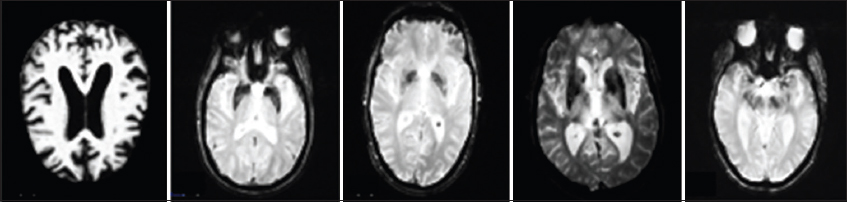

As illustrated in Fig. 1, AD has five stages: (1) AD dementia with severe symptoms, then (2) Late Mild Cognitive Impairment (LMCI), (3) Mild Cognitive Impairment (MCI): which is a condition that precedes dementia but does not meet the criteria for a diagnosis of AD, (4) Early Mild Cognitive Impairment (EMCI), (5) Cognitively Normal (CN): pre-clinical dementia, which is classified by the symptom-free period that occurs between the initial brain lesions and the onset of the first symptoms [7].

Fig. 1. Samples of magnetic resonance imaging images representing different Alzheimer’s disease (AD) stages. (1) AD, (2) Late mild cognitive impairment; (3) Mild cognitive impairment, (4) Early mild cognitive impairment, (5) Cognitively normal.